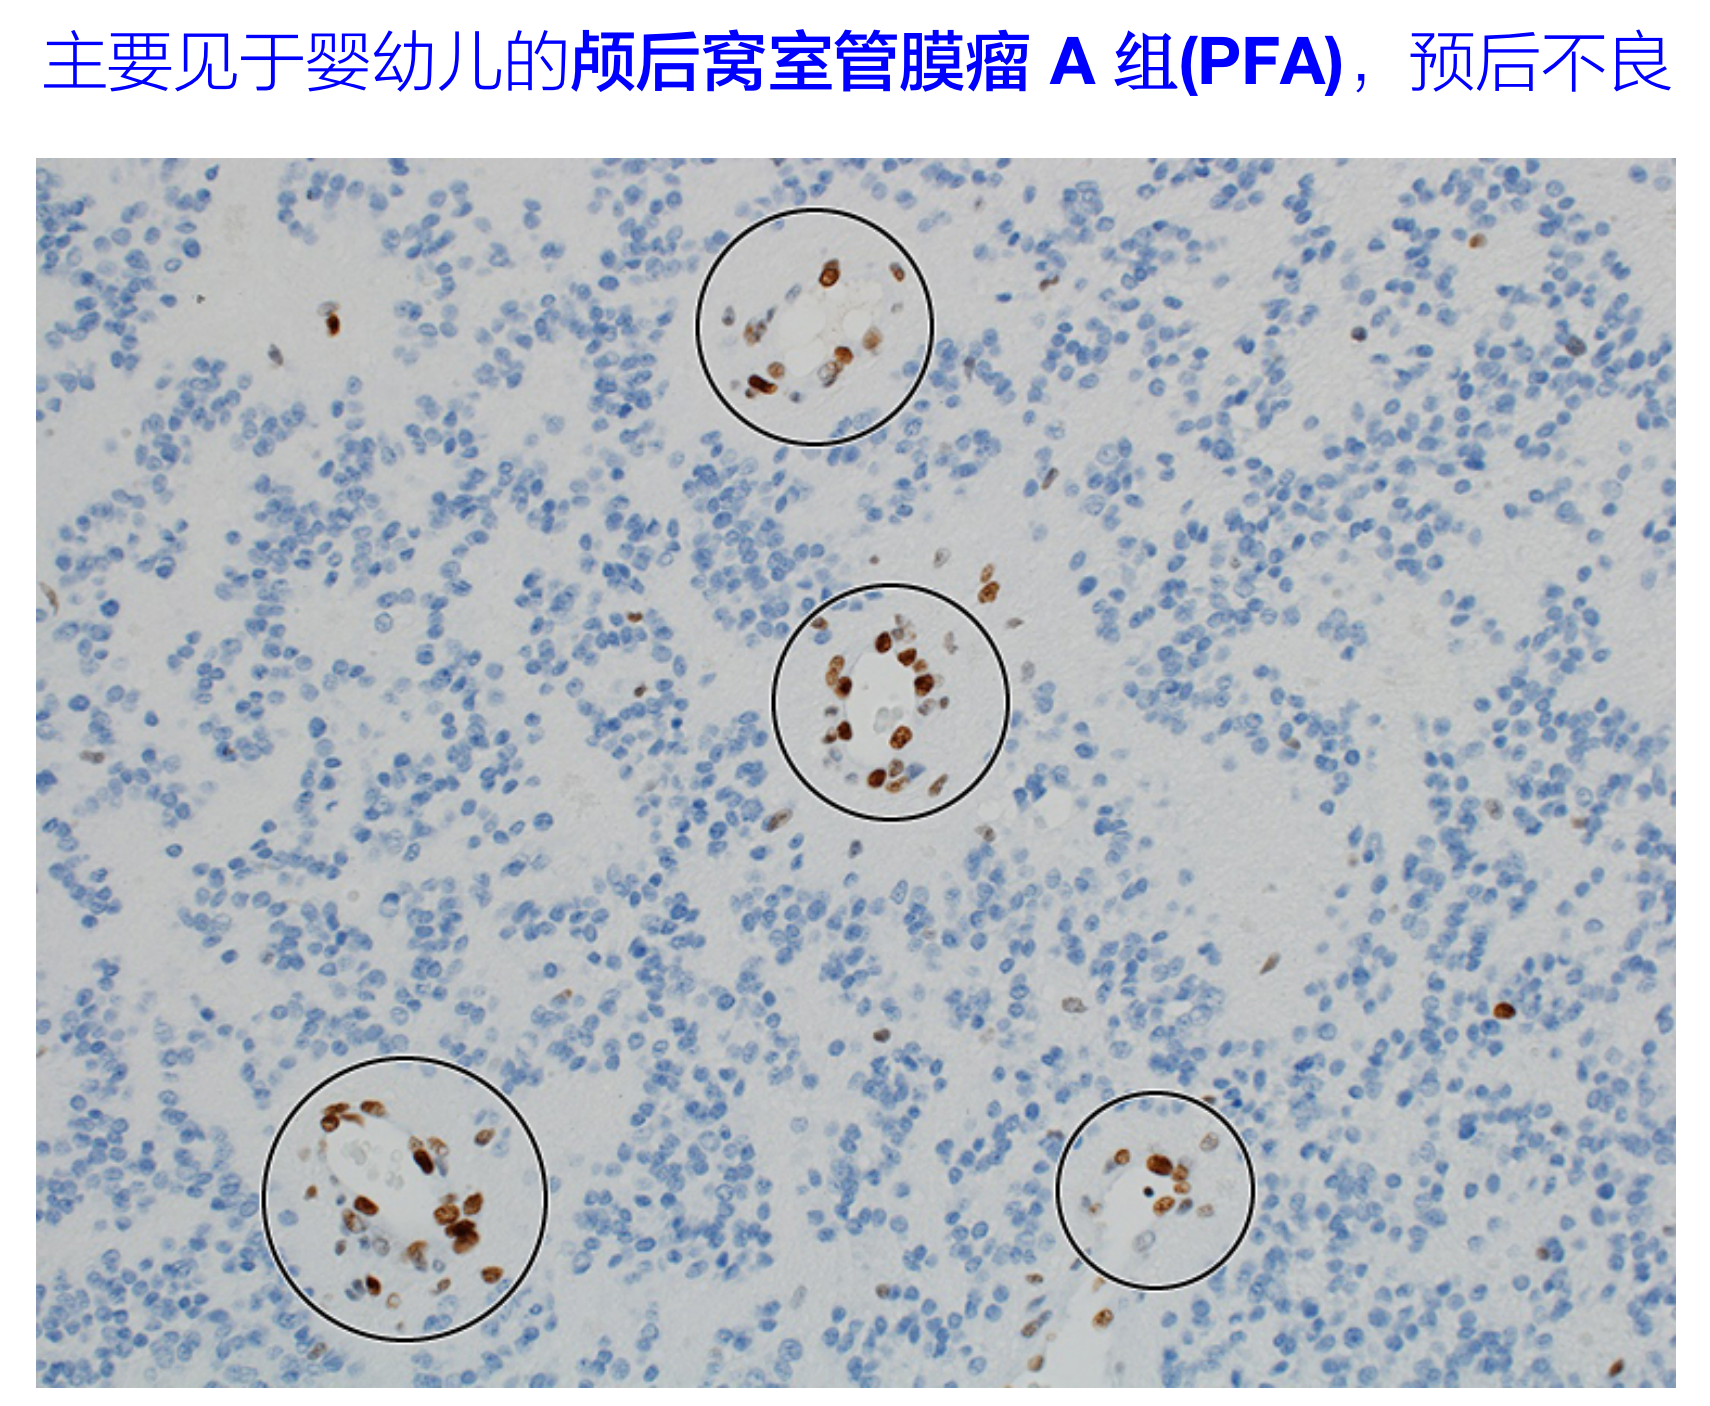

颅后窝室管膜瘤A组(PFA),预后不良,主要见于婴幼儿。